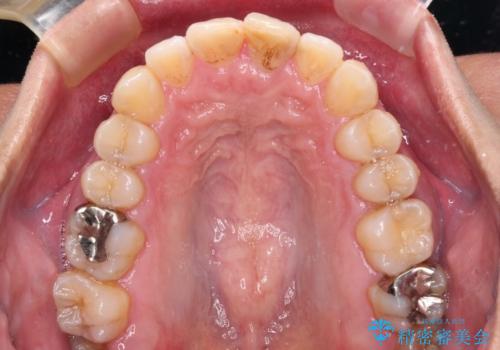

- 前歯のデコボコを気にして来院された患者様です。

下顎前歯のデコボコが特に強く、治療を早く終えることを考えるとワイヤー装置がお勧めですが、ワイヤー装置の異物感は避けたいのでインビザラインを希望されていました。

インビザラインで治療を行うか、ワイヤーで治療を行うかずっと悩んでいらっしゃいましたが、早く終わらせることを優先してワイヤー装置にて治療を行うこととしました。

下顎にワイヤー装置を装着し、暫くしたところでやはりインビザラインにて矯正治療をしたいとのことで、インビザラインに切り替えました。

短い期間でしたがワイヤー装置を使用したことでデコボコが解消されたため、インビザラインの比較的短い期間で矯正治療を行うことができました。